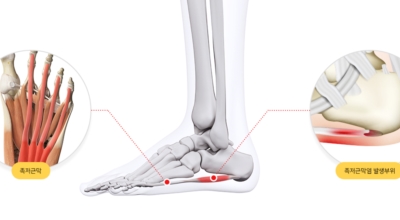

족저 근막이란 발가락 시작지점부터 발뒤꿈치뼈까지 발바닥 전체를 감싸고 있는 두꺼운 막을 말해요. 족저 근막은 발바닥 아치를 보존시켜 발바닥이 지면을 내딛음으로써 생기는 쇼크을 흡수하는 중요시되는 역할을 수행하고 있어요. 이 족저 근막에 일차적으로 서서히 조직 훼손이 일어나고 계속적인 활동에 의하여 염증이 커지면서 발 뒤꿈치 부근 통증을 일으키게 되는데 염증은 무리하고 반복적인 동작, 많은 활용으로 마찰에 의해 발생해요.

족저 근막염은 염증에 의한 훼손 및 통증을 유발하는 질환인데요 족저 근막염 증상은 동일한 발뒤꿈치 통증 하글런드 병변의 기형으로 알려져 있으고 아킬레스 건과 연관이 깊다고 해요. 특히 근육이 덜 풀린 아침 시간 대는 보행 시 날카롭고 바늘로 찌르는 듯한 심한 통증을 느끼게 된다고 해요. 하지만 아침 시간 대를 지나 오후에 접어들면서 일정 양 통증은 서서히 감소하기 시작한다고 하는데요 초기 증상이 나타난다면 필수로 전문의를 찾아 조기치료하는 것이 바람직해요.